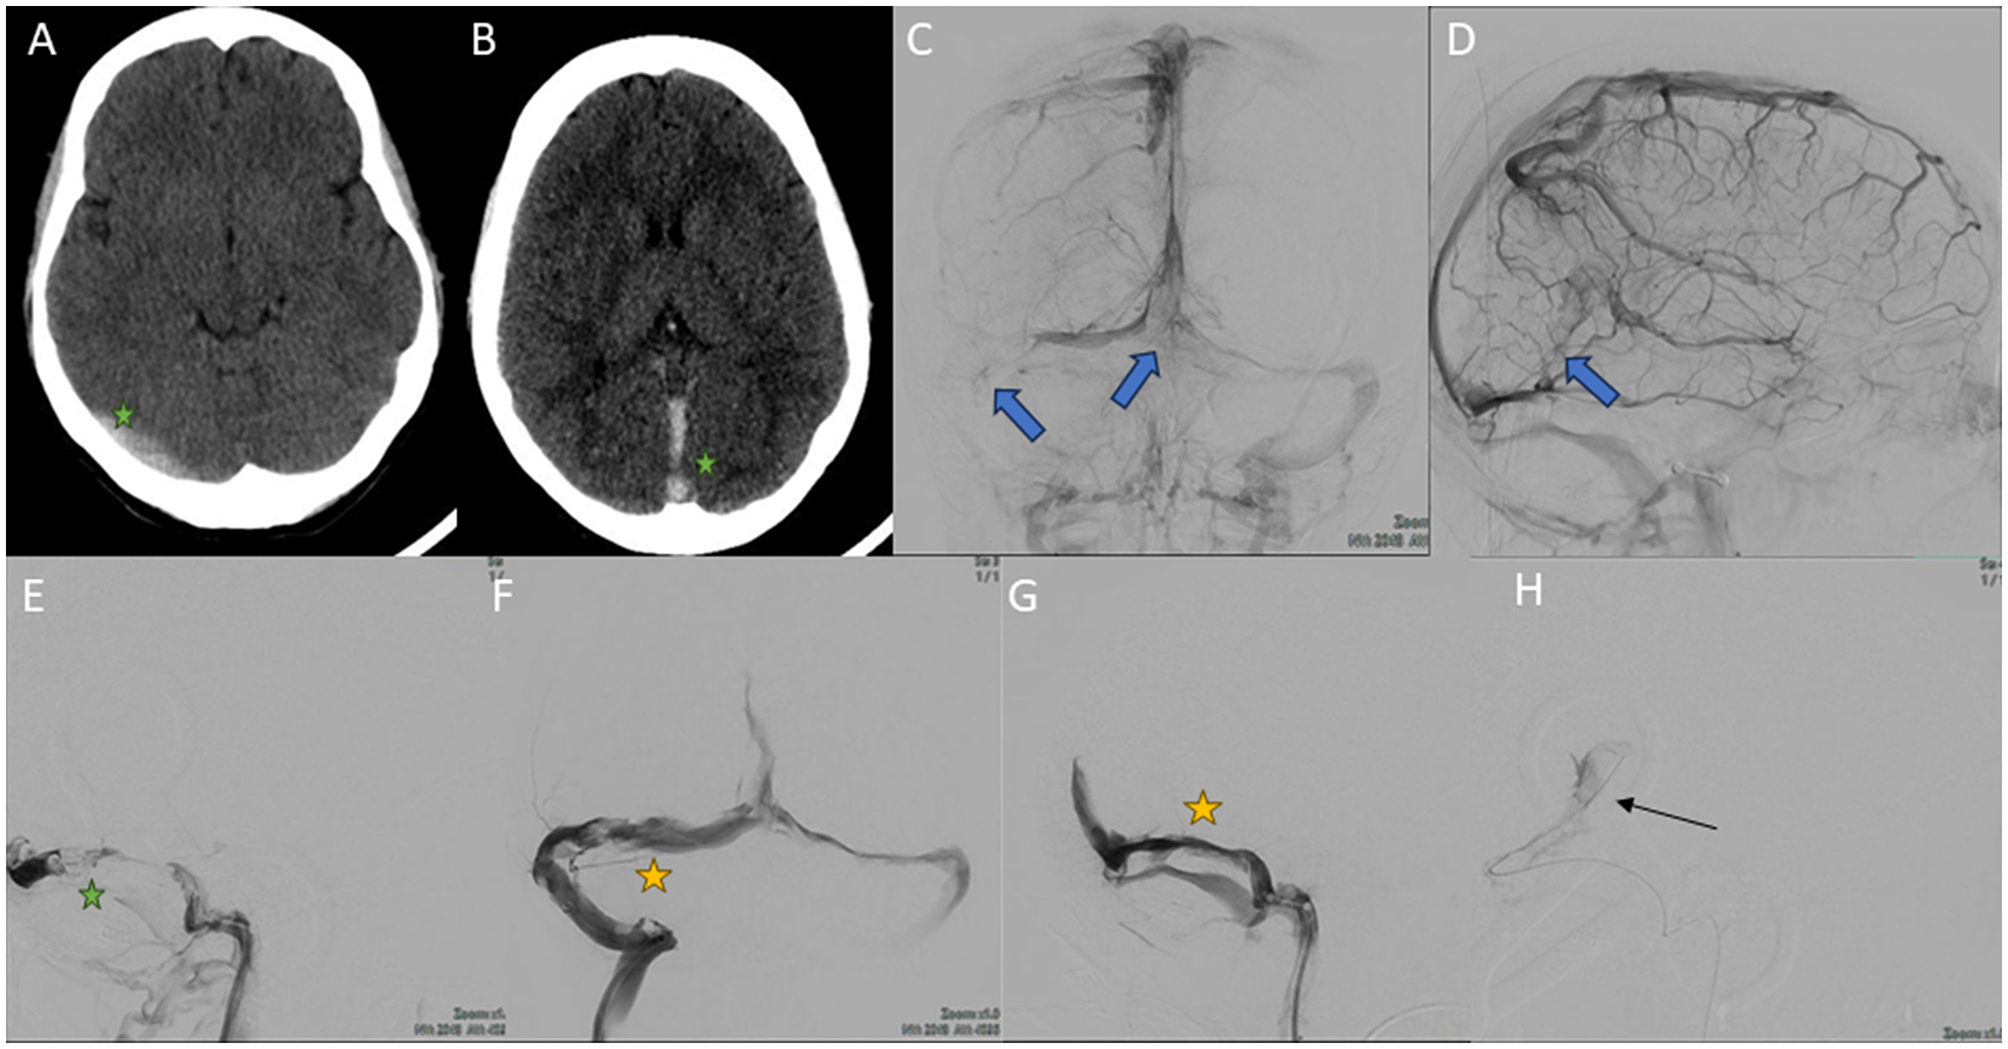

Figure 3. Images obtained during the course of case 2. (A, B) Cerebral CT scan without intravenous contrast. There is evidence of hyperdensity at the right transverse venous sinus, rectus sinus and superior sagittal sinus (green stars) due to acute thrombosis. (C, D) Selective right internal carotid arteriography in venous phase, anteroposterior (C) and lateral (D) view. Multiple repletion defects are evident in both transverse sinuses [blue arrow in (C)], torcula [blue arrow in (C)], superior sagittal sinus, rectus sinus and deep cerebral venous system [blue arrow in (D)], secondary to thrombosis. (E–H) Cerebral venography obtained by left internal jugular access, MT. (E) Lateral view. Occlusion of the right transverse sinus (green star). (F) Anteroposterior view. Recanalization of the right transverse sinus after endovascular treatment (yellow star). (G) Lateral view. Occlusion of the rectus sinus is seen (yellow star). (H) Lateral image view. Microcatheter (black arrow) is advanced through the rectus sinus prior to recanalization by stent retriever with TigerXL® device (not shown in the image).

Urgent cerebral arteriography was performed, which showed evidence of large CVT, again with DCVT (Figures 3C, D). MT was performed with Neuron MAX 0.88® and JET7® devices, as well as with a stent retriever (Tiger XL®) (Figures 3E–H). A 4F diagnostic catheter was placed in the right internal carotid artery for successive diagnostic series. Cerebral venous circulation was accessed by puncture of the right internal jugular vein by placing a guide catheter into the sigmoid sinus and the beginning of the transverse sinus. Successive aspirative MT were performed on the left transverse dural sinus, right transverse sinus, superior sagittal sinus, and with stent retriever in the rectus sinus (total passes: 6), removing again a large amount of clot. Final controls showed complete recanalization of the dural sinuses (Figures 4A, B). Cranial CT scan performed 24 h after MT showed no ischaemic or hemorrhagic complications. Neurological recovery was complete in the following days, with papilledema predominantly in the right eye and headache that improved with simple analgesia. As part of the etiological study, a complete blood analysis was performed, which only showed hypohomocysteinemia (2.1 μmol/L), the remainder being normal (including the thrombophilia study). The study was completed with cerebral MRI with angioMRI at 7 days, with no evidence of venous infarction and nearly complete recanalization of the venous system (Figures 4C–E). At discharge, intravaginal contraception was suspended and treatment was started with folic acid 5 mg/24 h and anticoagulation with acenocoumarol (vitamin K inhibitor). The modified Rankin Scale was 0 at discharge at 3 months.